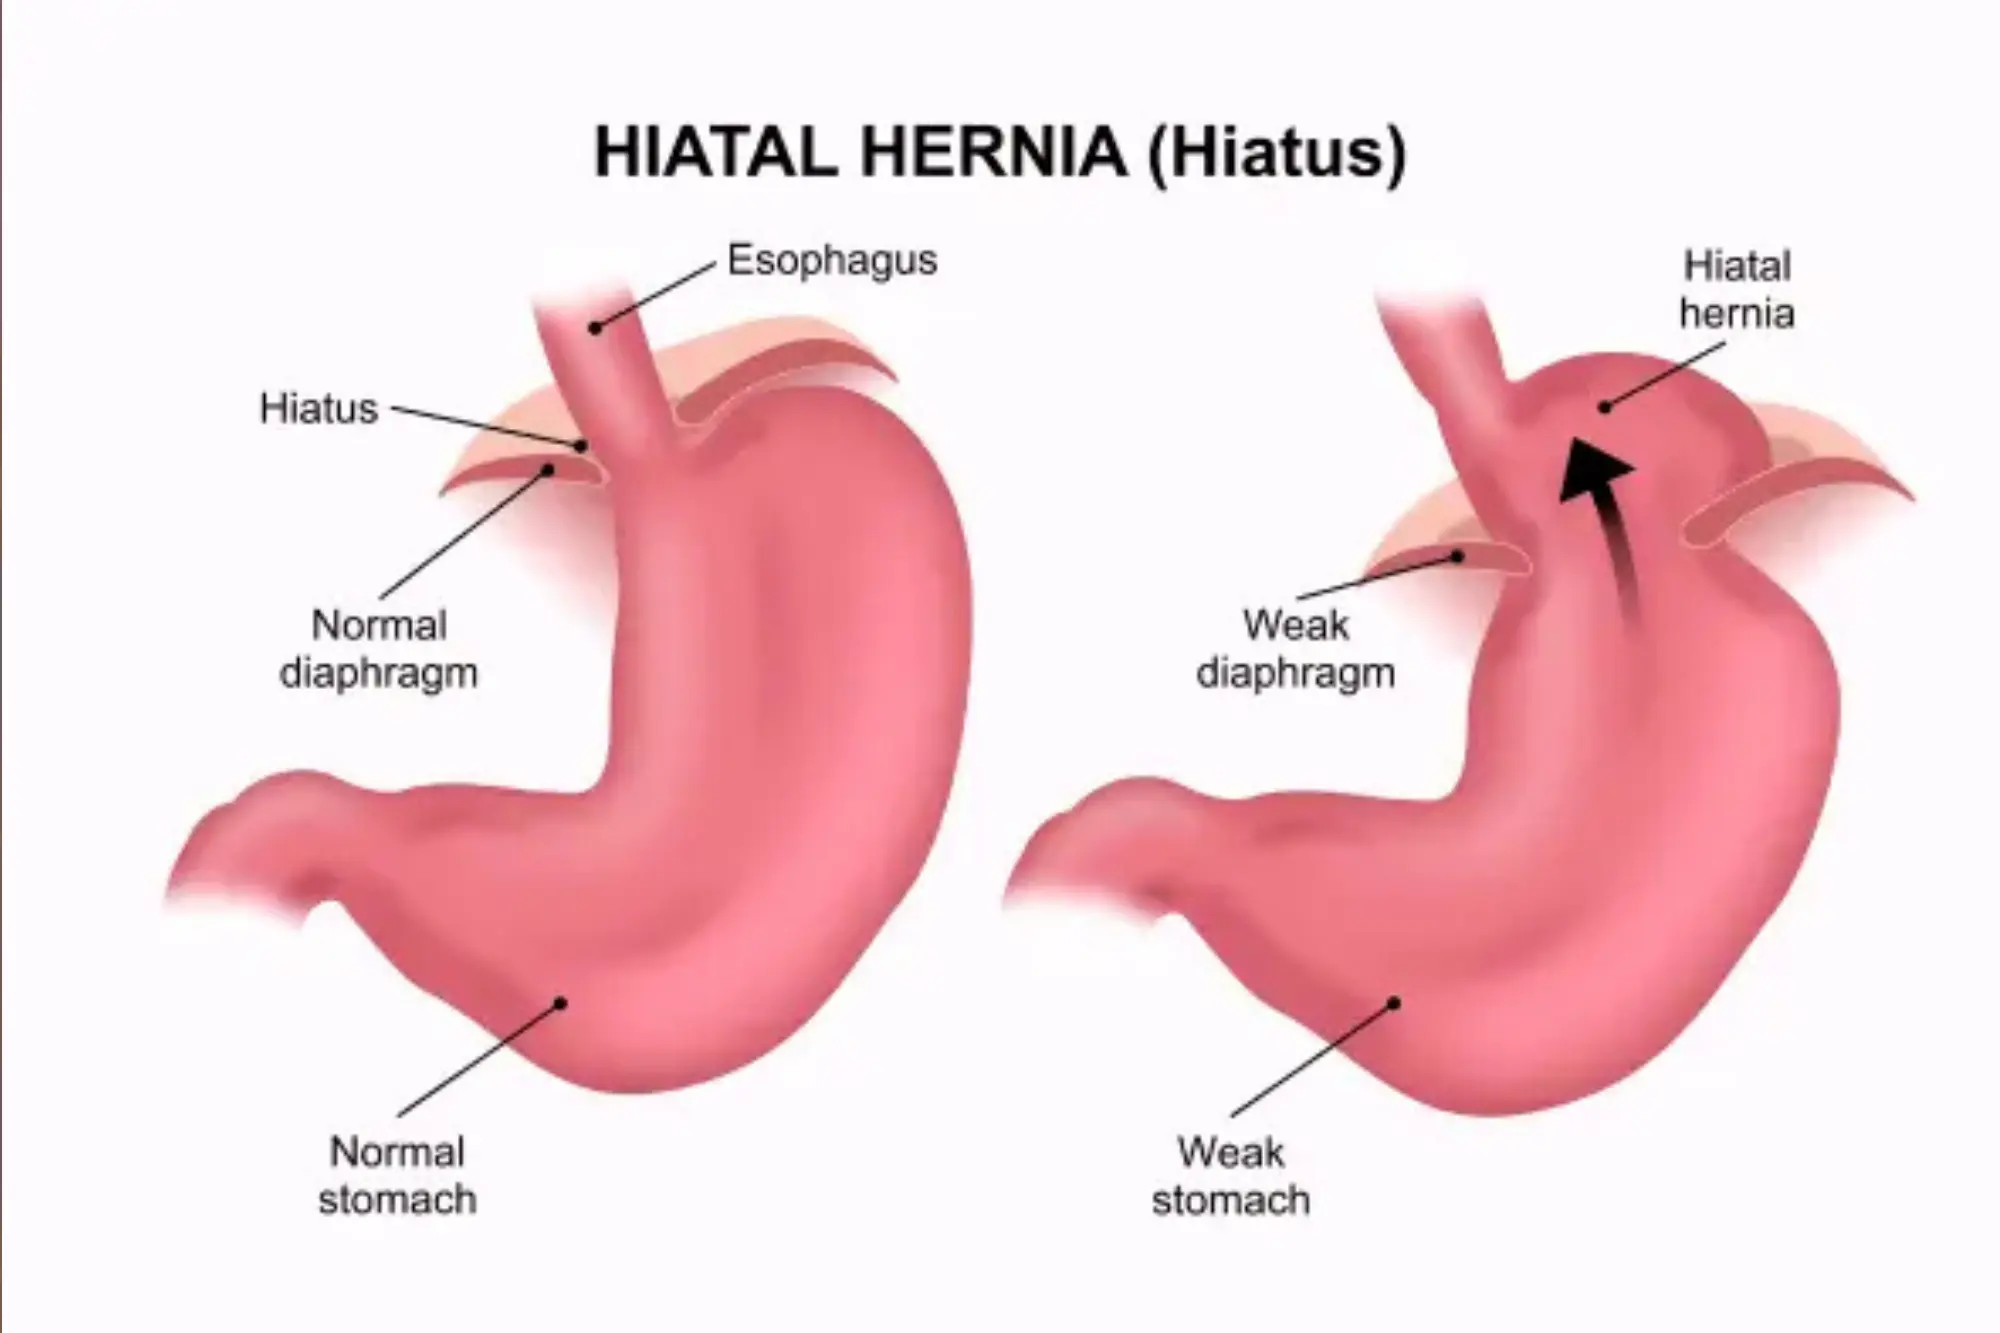

Hiatal hernia

A hiatal hernia occurs when the upper part of the stomach pushes through the diaphragm into the chest cavity